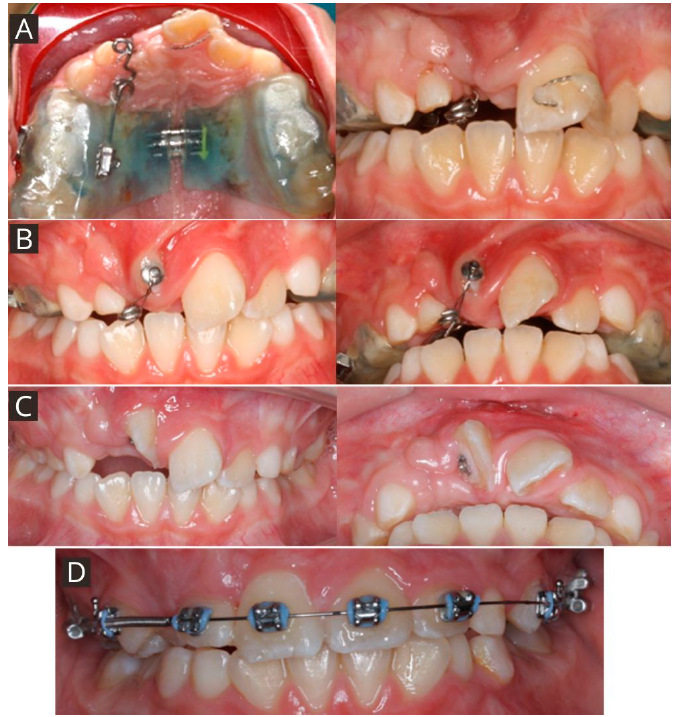

El abordaje quirúrgico del diente 11 se realizó con exposición quirúrgica cerrada llevada a cabo por un cirujano maxilofacial y en el acto quirúrgico se instalaron un botón vestibular y uno palatino de refuerzo con ligadura de acero inoxidable de 0.9 FH para la tracción. Se realizó la desinclusión del supernumerario previo a la cirugía de exposición dentaria. Se realizó la instalación de disyuntor McNamara con extensión palatina acrílica, brazo de tracción palatino con alambre 0.9 FH y tornillo central simple con ¼ de activación diaria por 20 días para lograr una expansión de 5 milímetros (Figura 6. A). Se agregaron tubos vestibular y palatino en el disyuntor para un eventual cantilever de titanio beta molibdeno (TMA). Se empleó disyunción maxilar acorde a lo planificado y 15 días posterior a la cirugía se activó el brazo de tracción palatino con una fuerza de 50 gramos (Medidor de tensión VTSYIQI model ATG-500-2 ®) aproximadamente cada cuatro semanas, dejando la encía del reborde marginal levemente isquémica.

Figura 6 Fotografías clínicas de seguimiento. A. Instalación de disyuntor McNamara con extensión palatina acrílica, brazo de tracción palatino con alambre 0.9 FH y tornillo central simple. B. Control a las 20 semanas de tracción. C. Control a las 28 semanas de tracción. D. Instalación de aparatología fija para la alineación y nivelación del grupo incisivo superior.

A las 20 semanas se observó exposición de botón vestibular del diente 11 (Figura 6. B), retirando a las 28 semanas el disyuntor (Figura 6. C) e instalando aparatología fija para la alineación y nivelación del grupo incisivo superior, donde se realizó la misma secuencia del primer caso: brackets autoligantes prescripción cco 2x4 para una mejor alineación del grupo incisivo superior con una secuencia de arco NiTi termoactivado 0.014” - 0.016” - 0.018” - 0.017” x 0.025” y luego arco de acero 0.019” x 0.025”. Como refleja la Figura 6. D fue posible observar la evolución de 1 año de tratamiento con aparatología fija. Durante la tracción se utilizó solo el botón vestibular para generar un vector de fuerza más favorable con sentido posteroinferior y así, mejorar el pronóstico periodontal del diente 11. No se utilizaron los tubos añadidos al disyuntor.